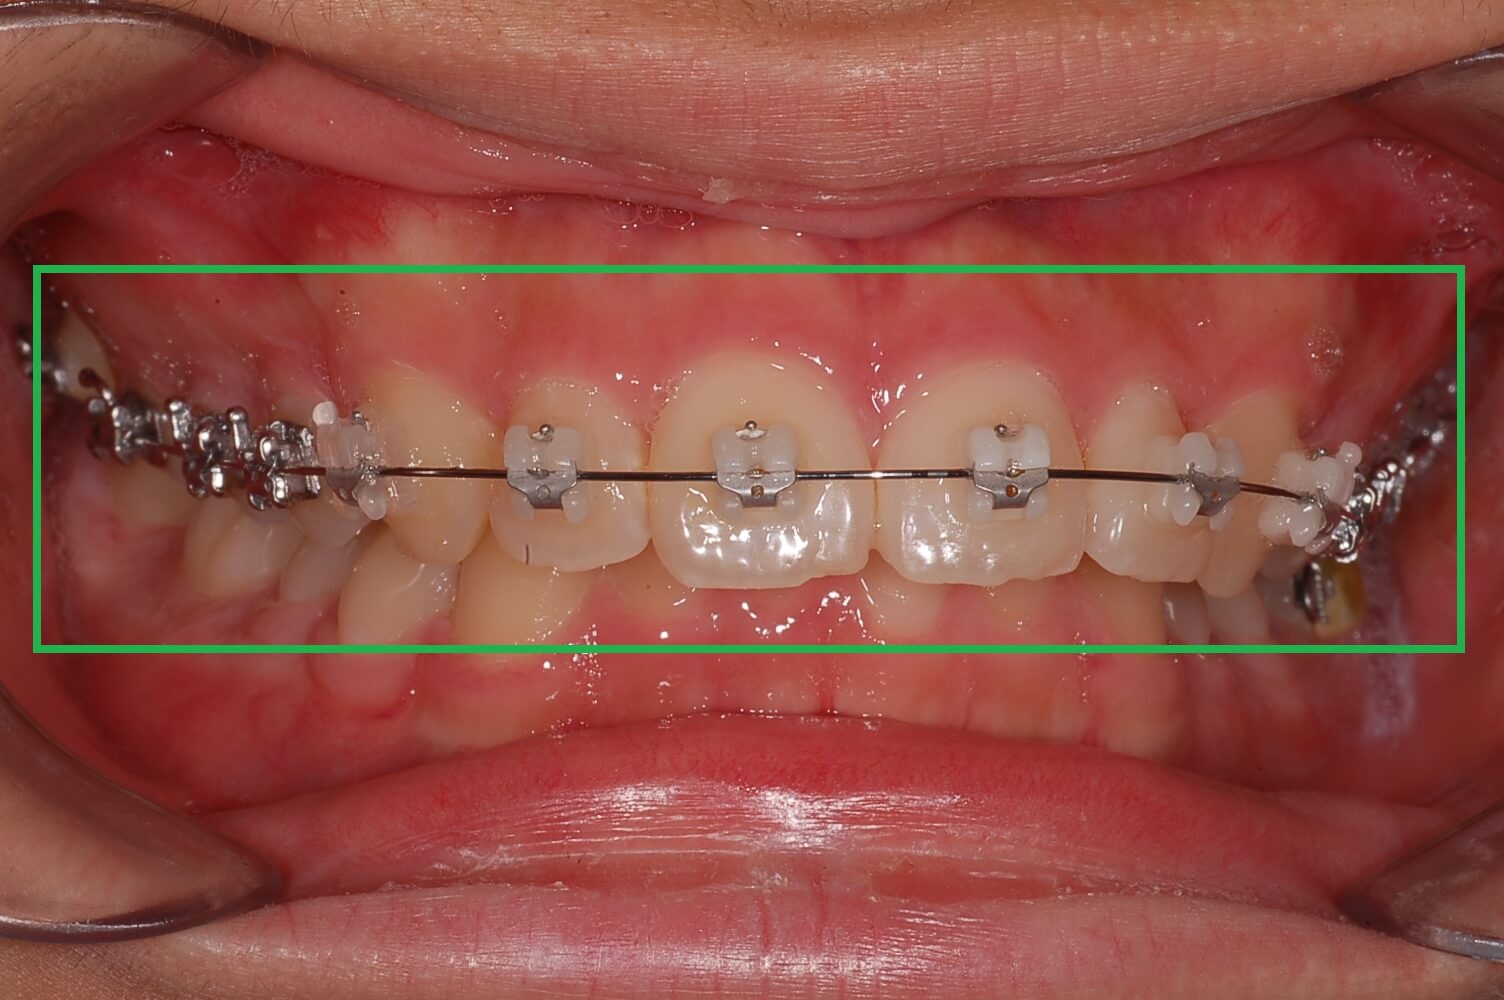

3. 가위교합 + 과개교합 교정실시 (전체브라켓 부착)

3개월간 가위교합 교정이 들어갔고 어느 정도 어금니가 제자리로 돌아왔습니다. 과개교합 교정을 위해 전체브라켓을 부착 하고 있는 사진입니다.

사진에 보면 철사가 S자 모양으로 휘어져 있습니다. 이 철사가 일자형으로 복원이 되면서 틀어진 치아배열을 정돈한다고 하는데 정확한 전문지식은 아니니 참고만 해주세요.

▼ 어금니 교정 후 전체 브라켓 부착

전체 교정 브라켓을 부착 후 2달 정도 지나고 나니 S자로 휘어진 철사가 어느 정도 일자로 복원되면서 앞니의 치아배열이 가지런하게 정리가 되어있습니다.

▼ 5개월 교정 후 사진(1)

▼ 5개월 교정후 사진(2)